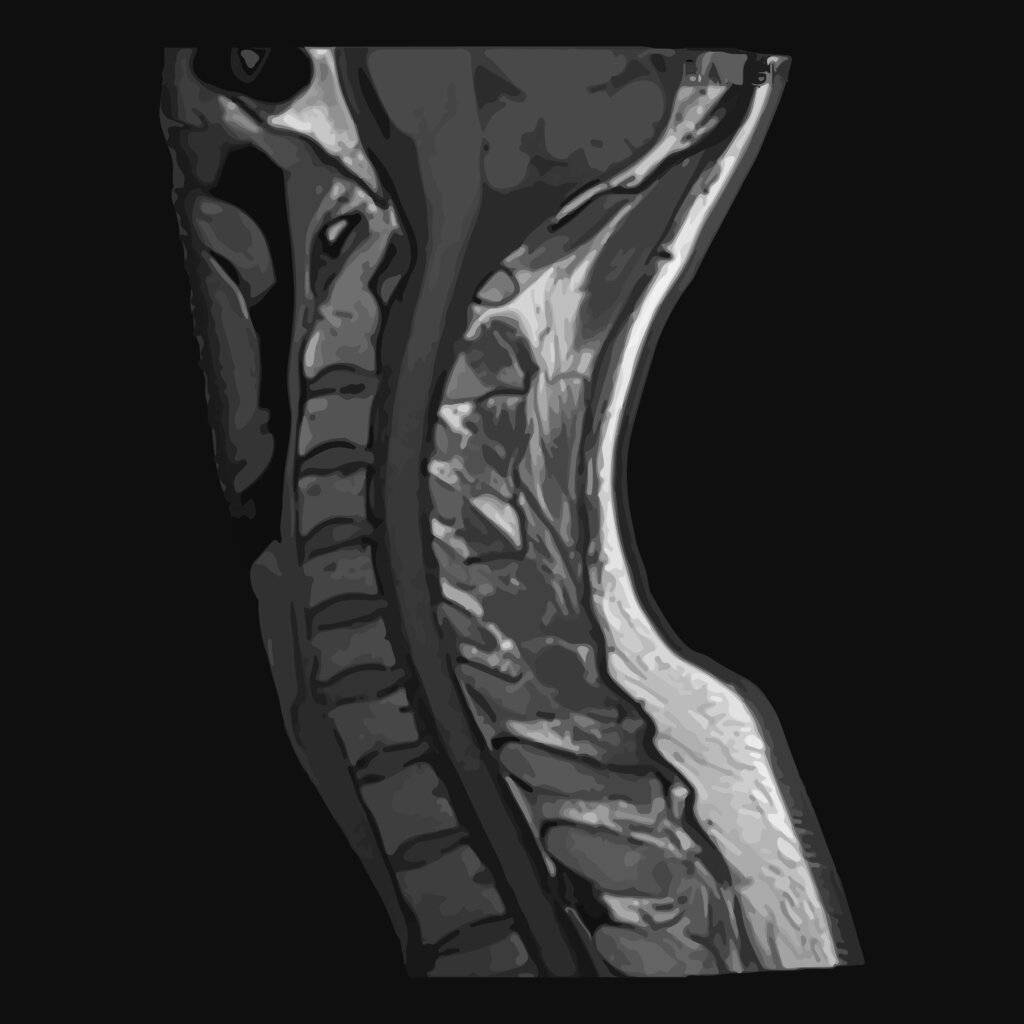

Die MRT hingegen nutzt starke Magnetfelder und Radiowellen, um detaillierte Bilder von Weichteilen wie Rückenmark, Bandscheiben und Nerven zu liefern. Die Entscheidung für eine der beiden Methoden hängt vom klinischen Kontext und den spezifischen diagnostischen Anforderungen ab.

CT Bilder Wirbelsäule

Die Wirbelsäule ist eine komplexe Struktur mit zahlreichen Knochen, Bandscheiben, Bändern und Nerven. Die CT-Bildgebung der Wirbelsäule kann diese komplizierte Anatomie mit außergewöhnlicher Klarheit erfassen. Diese Detailgenauigkeit ist für die Diagnose zahlreicher Erkrankungen wie Frakturen, degenerative Veränderungen, Spinalkanalstenose und Tumore unerlässlich. Darüber hinaus können CT-Bilder dazu beitragen, die Ursache von Rückenschmerzen oder neurologischen Symptomen zu ermitteln, indem sie Probleme sichtbar machen, die auf Röntgenbildern möglicherweise nicht zu erkennen sind.